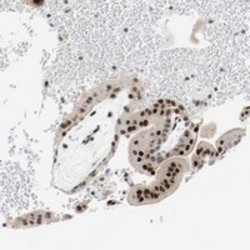

- Experimental details

- Immunohistochemical staining of human placenta with ASH1L polyclonal antibody (Cat # PAB20281) shows strong nuclear positivity in trophoblastic cells at 1:50-1:200 dilution.

- Validation comment

- Immunohistochemistry (Formalin/PFA-fixed paraffin-embedded sections)